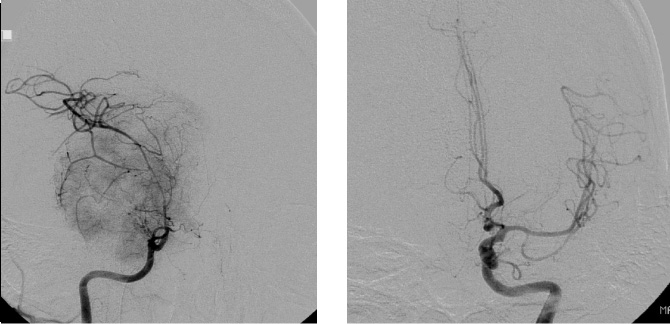

症例3は42歳女性。意識消失にて発症。CT、MRIにて内頸動脈、中大脳動脈を巻き込む大型の前床突起部起源の髄膜腫を認める。

中大脳動脈の血流が低く、血管損傷を来す可能性もあるので、浅側頭動脈-中大脳動脈バイパスをおいた後に腫瘍内より血管を掘り起こすように摘出を行った。

細い脳深部に至る血管も保護して摘出した。術後四肢麻痺等なく回復。

術前画像:内頸動脈などの血管を巻き込み狭窄する(反対側と比較)腫瘍をみとめ周囲に脳の腫れを認める。

術後画像:腫瘍はほぼ摘出され、脳梗塞等の合併症は認めない。